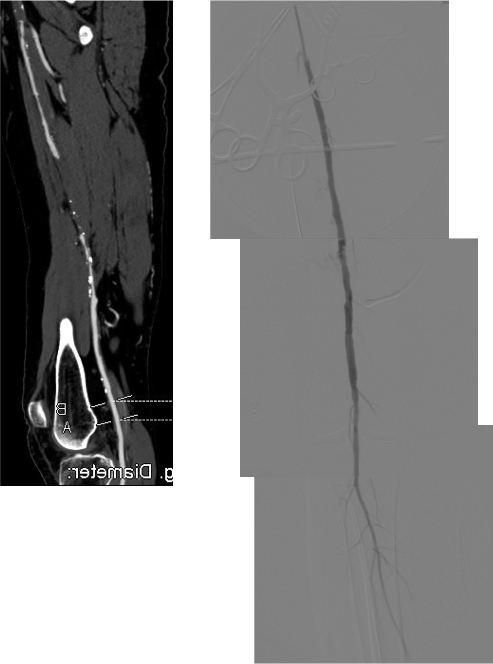

On examination, he had heavy scarring in both groins from prior open incisions healed by secondary intention, a midline laparotomy incision. He had weak bilateral axillary and brachial artery pulses. He had no pulses in either leg. The right foot had gangrene of the distal phalanx of the third toe. The both feet were anemic and painful -the left foot had more dependent rubor. Pulse volume recordings were flat in both legs. TCPO2 was in the 20-40mmHg range at the thighs bilaterally suggesting reduced potential for healing an above knee amputation. Vein mapping showed no suitable saphenous vein in either leg. CTA (figure below) showed both external iliac arteries to be occluded or absent and the common femoral arteries to be occluded or missing bilaterally.

The left femoral bifurcation was preserved and the left SFA was patent into small underfilled tibial vessels. On the right, there was an isolated segment of profunda femoral artery that reconstituted from pelvic collaterals. The right below knee popliteal artery reconstituted and had underfilled but patent three vessel runoff (figure below).